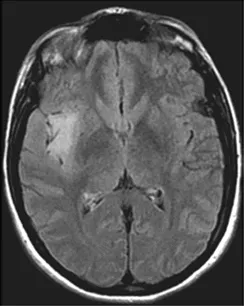

2008年5月,当我因剧烈头痛无法工作时,做了脑部MRI检查,显示一个小的动脉瘤以及右侧岛叶病变,提示可能是一个胶质瘤(图1)。此时的我只知道脑子里面长了东西,有一些恐惧,但是还没有真正意识到问题的严重性。

图1:2008年5月轴向FLAIR磁共振图像显示,右侧岛叶低级别胶质瘤,肿瘤体积为3cm³

当时,医院使用一种专门的工具,计算了我第一次和最后一次MRI检查的肿瘤体积。2008年5月,刚查出时,肿瘤体积为3cm³(图1),而在最后一次检查,2013年11月时,病变体积为11cm³(图2)。